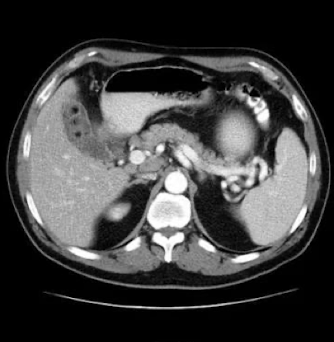

What is this and what type of scan

Polycystic kidney disease, CT scan